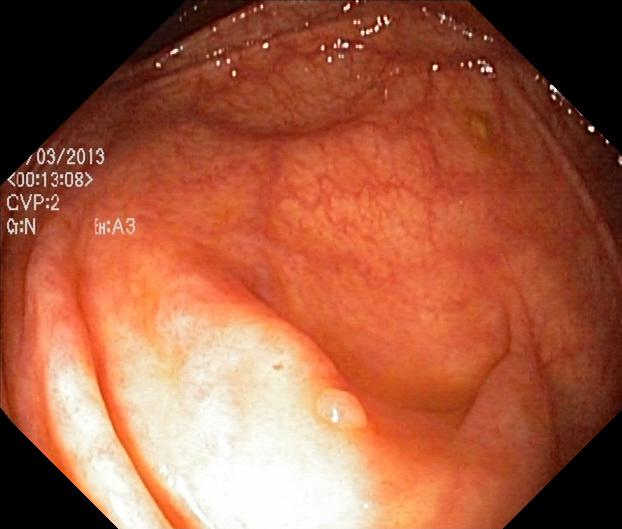

The Kvaris-SEG (Jha et al., 2020c) training dataset can be downloaded from https://datasets.simula.no/kvasir-seg/. It contains 1,000 polyp images and their corresponding ground truth mask as shown in Figure 1. The dataset was collected from real routine clinical examinations at Bærum Hospital in Norway by expert gastroenterologists. The resolution of images varies from to pixels. Some of the images contain a green thumbnail in the lower-left corner of the images showing the scope position marking from the ScopeGuide (Olympus) (see Figure 2). We annotate another separate dataset consisting of 160 new polyp images and use the resulting dataset as the test set to benchmark the participants’ approaches. Figure 2 shows some examples of test images used in the challenge.